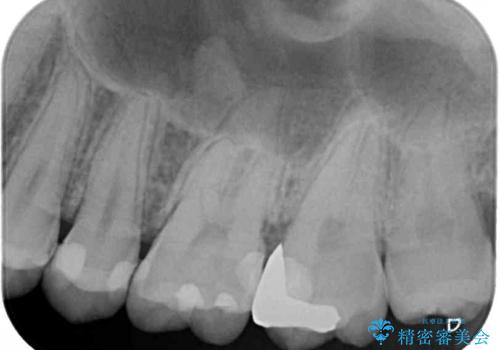

- 奥歯にフロスが引っかかるようになり、虫歯ではないかとのことで来院された患者様です。

レントゲン写真より、左右奥歯にむし歯があることが分かりました。

奥で目立たないことから、虫歯の再発リスクが最も低く、咬合力による歯への負担も少ないゴールドインレー(PGAインレー、白金加金インレー)にて修復治療をすることとしました。